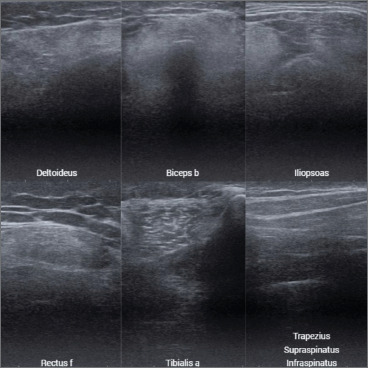

Case report: An 8-year-old male presented with muscle weakness since birth, delayed motor milestones, toe walking, and frequent falls. Family history revealed maternal-line neuromuscular disorders. Clinical examination showed hyporeflexia, thoracic hypotrophy, and decreased proximal muscle strength, alongside joint hypermobility and keratosis pilaris. Electromyography indicated a myopathic pattern in proximal upper limb muscles. Genetic analysis confirmed a pathogenic COL6A1 variant (c.788G > A, p.Gly263Asp). Ultrasound findings revealed advanced structural compromise with Heckmatt grade IV echogenicity in the deltoid, iliopsoas, and rectus femoris, indicating fatty infiltration and fibrosis. Functional tests, including Motor Function Measurement (MFM), showed adequate performance despite significant structural abnormalities.